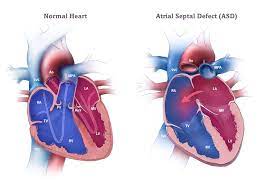

Overview

Package includes:

Days in hospital : 7 to 8 Day (For patient and one attendant)

Days in hotel : 14 Days (For patient and one attendant)

Room type in hospital : Shared

Room type in hotel : Private

Hotel category: Standard

Value added benefits of the ASD Surgical Closure Open Surgery:

Ø Doctor consultation charges

Ø Lab tests and diagnostic charges

Ø Room charges inside hospital during the procedure

Ø Surgeon Fee

Ø Nursing charges

Ø Hospital surgery suite charges

Ø Anesthesia charges

Ø Routine medicines and routine consumables (bandages, dressings etc.)

Ø Food and Beverages inside hospital stay for patient and one attendant.

Extra benefits:

ü Interpreter

ü Visa assistance

Ø Site tourism of the city

Ø Follow up with the doctor

Ø Airport pick up and drop

Ø Free online consultation with the doctor

Ø Priority appointments with the doctor

Ø Room upgrade from sharing to private